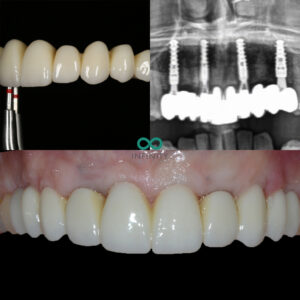

After a thorough clinical and CBCT scanning assessment we provided the patient with the option to have her failing teeth replaced with 4 dental implants and a permanent implant supported bridge. We also recommended a bone and gum graft to ensure that the damage done by her periodontal disease could be restored to build a stronger foundation for her dental implants.

During the treatment we provided our patient with fixed teeth from the very beginning of her treatment plan. She never spent any time without teeth. In fact, on the very same day that she had her teeth removed, we provided her with fixed dental implant supported teeth.

Dental implants, gums and bone grafts all take on average 3-6 months to fully stabilise after healing. This means it can take upto 6 months to provide a perfectly fitting set of teeth to the dental implants. During this time however, our patient continued to wear her initial implant supported teeth meaning she still had a lovely smile and could chew properly during this treatment time.

After the 6 months had passed, we carefully sculpted her gum line with all the volumous gum graft that had now worked and fully healed. The contours we had created were carefully designed to mimic her natural smile design that we planned using our digital smile desgin programmes. Following this careful gum sculpting process, we made a truly bespoke implant bridge that looked and felt as natural as is possible. The patient was delighted and we were especially proud of the fit between the gums and the implant teeth. That new gum line was healthy, natural and therefore very easy for the patient to clean and maintain daily with a normal electric toothbrush.